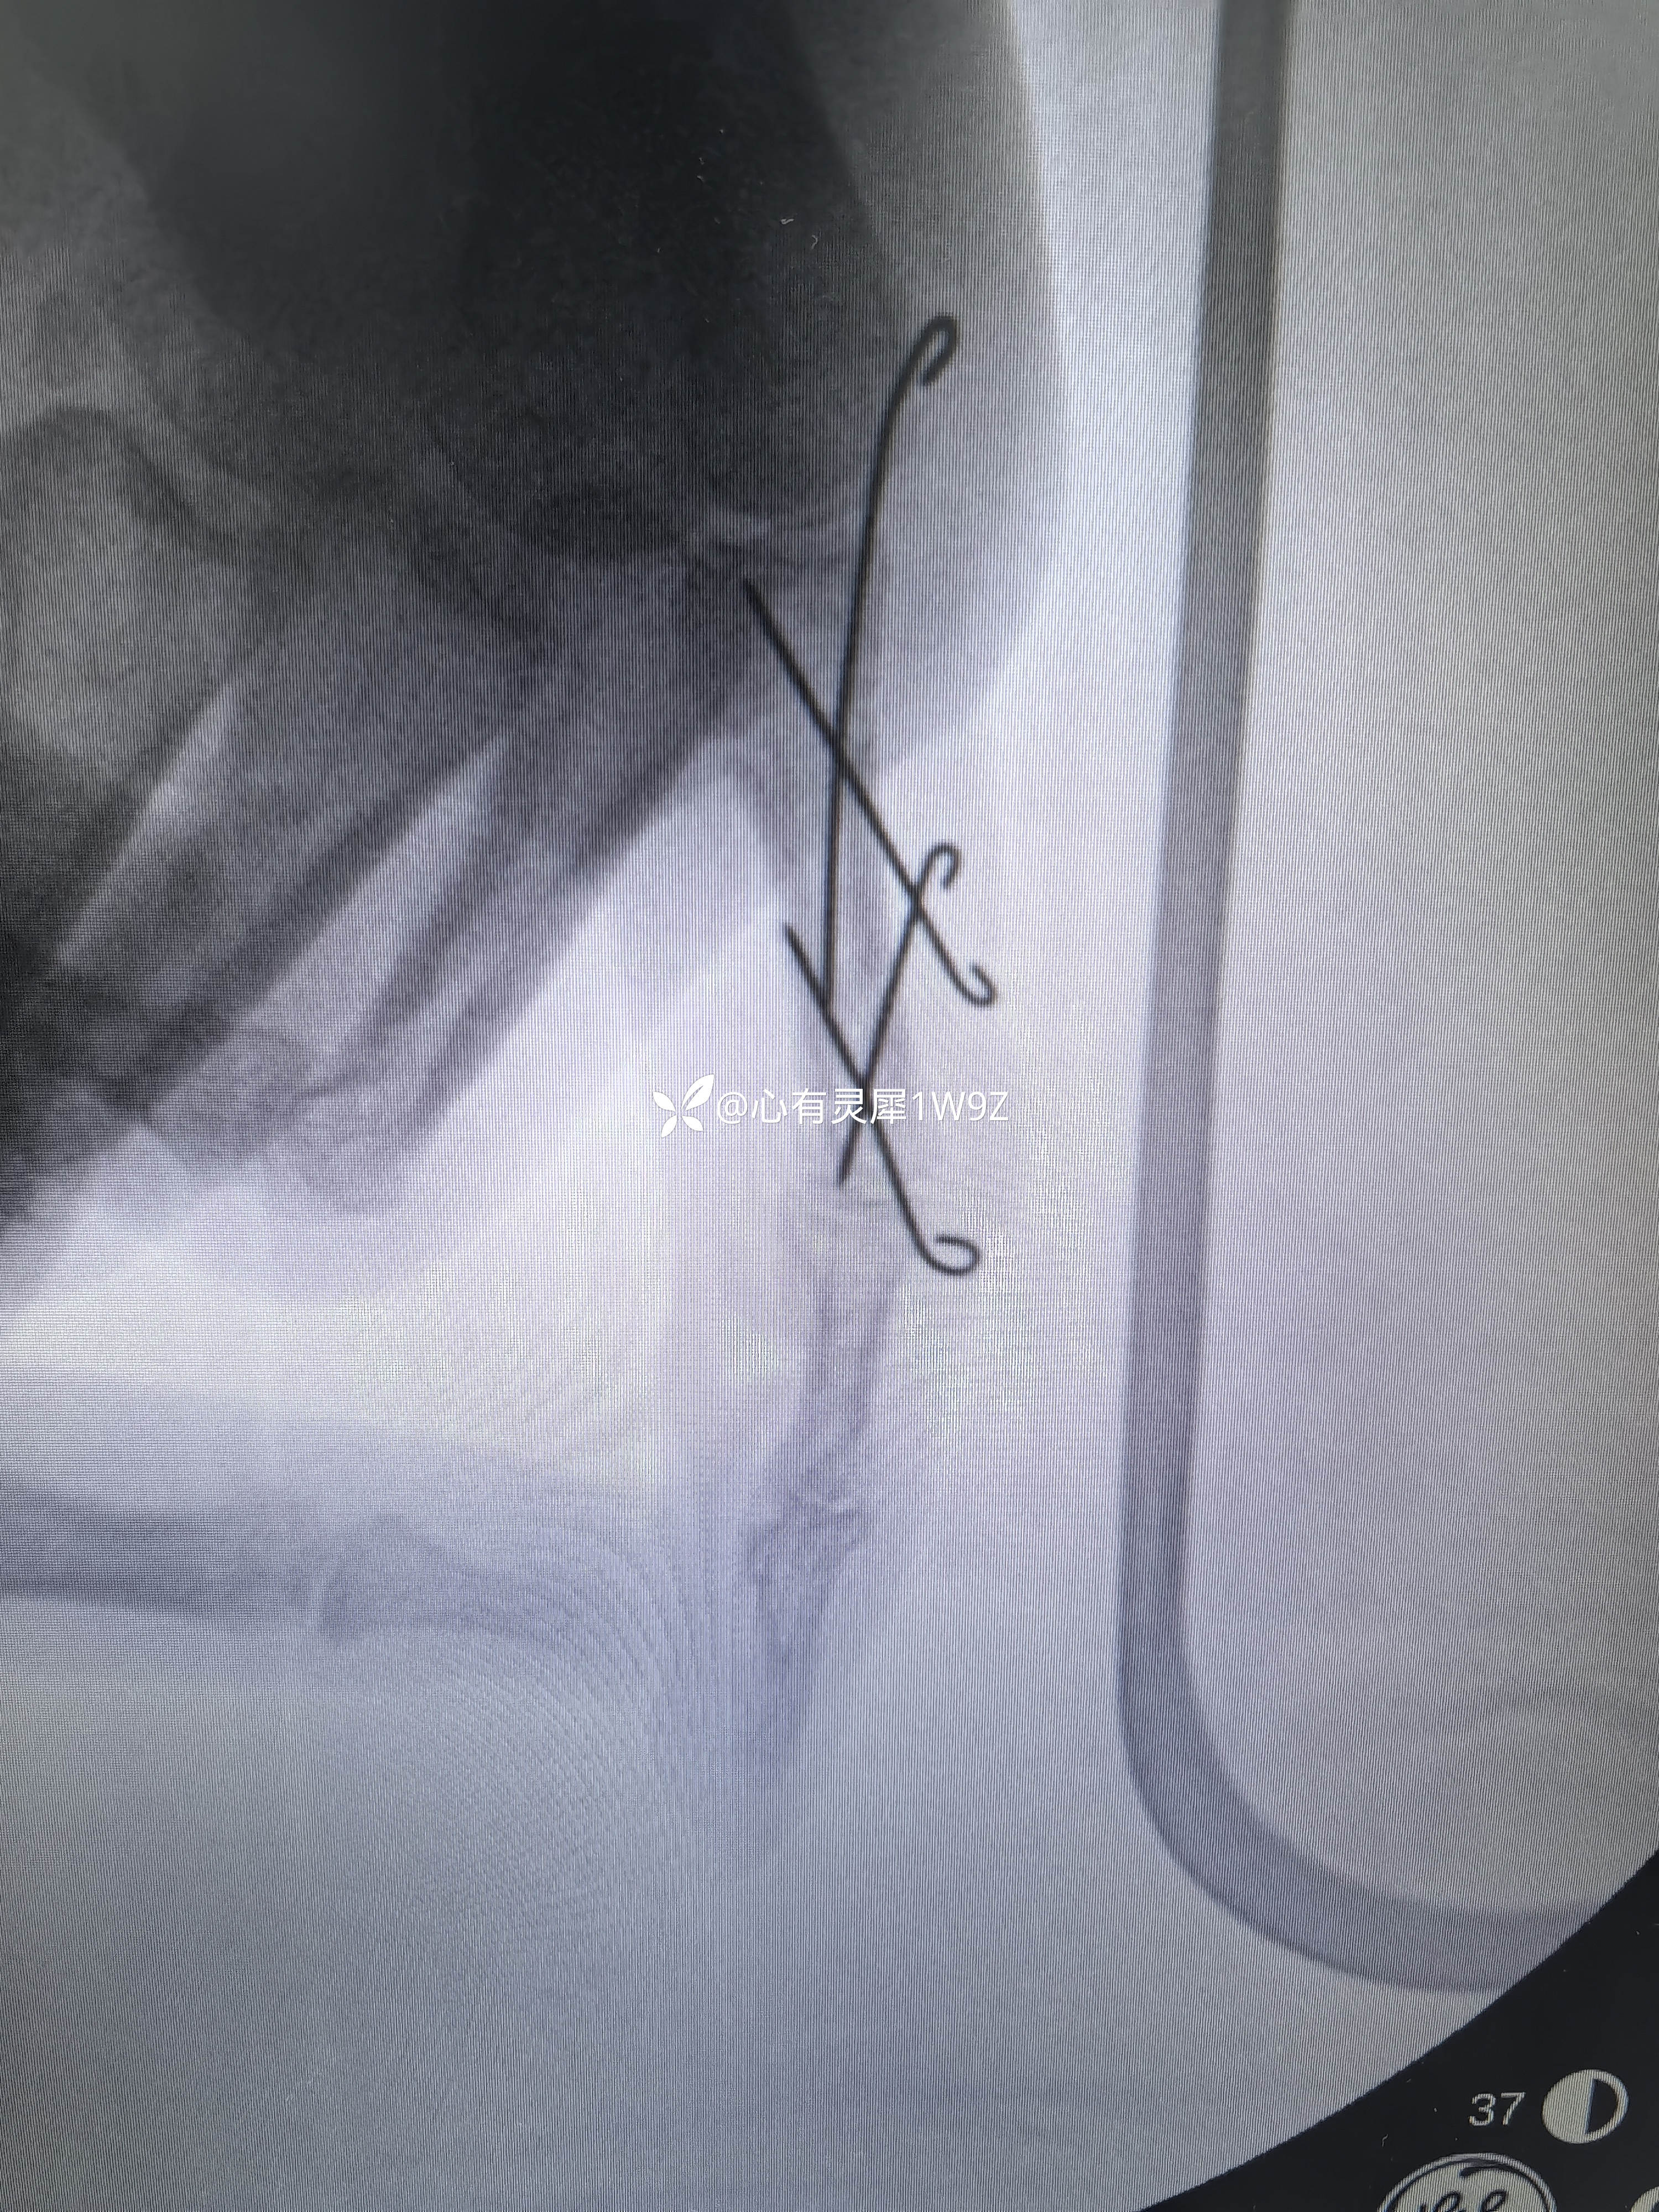

小指近节指骨两处骨折

【临床诊断】:左手小指近节指骨骨折

1.如何设计克氏针固定方案更合理2.术后需要石膏辅助固定吗?3多长时间开始小指屈伸锻炼?4多长时间拔针,一次拔针还是分两次拔针?